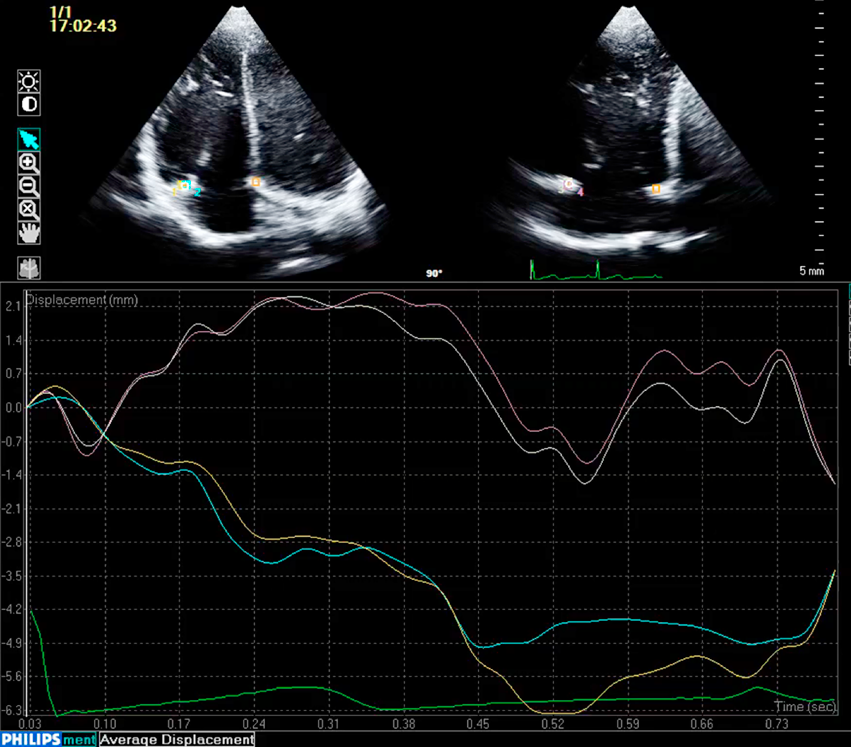

Tissue motion annular displacement, a function of QLAB 9.0 (Philips Medical Systems, Best, The Netherlands), was used to measure the diameter of the apical 4-chamber view in the septolateral direction (A) and the diameter orthogonal to this in the anteroposterior direction (B) by tracking the annulus during 1 cardiac cycle (Fig. 1). Assuming the annulus to be elliptical, we calculated its area using the 2 diameters with the following formula: annulus area=πAB/4. This was measured at each phase of the cardiac cycle to analyze the change in the tricuspid annulus area between phases. For the comparisons, we used values normalized to body surface area (annulus area / body surface area).

Fig. 1 X-plane tissue tracking

2D TTE X-plane image of normal tricuspid valve: upper two lines are AP diameter, lower two lines are SL diameter. Lines show diameter change during one cardiac cycle. AP: Anteroposterior, SL: Septolateral.